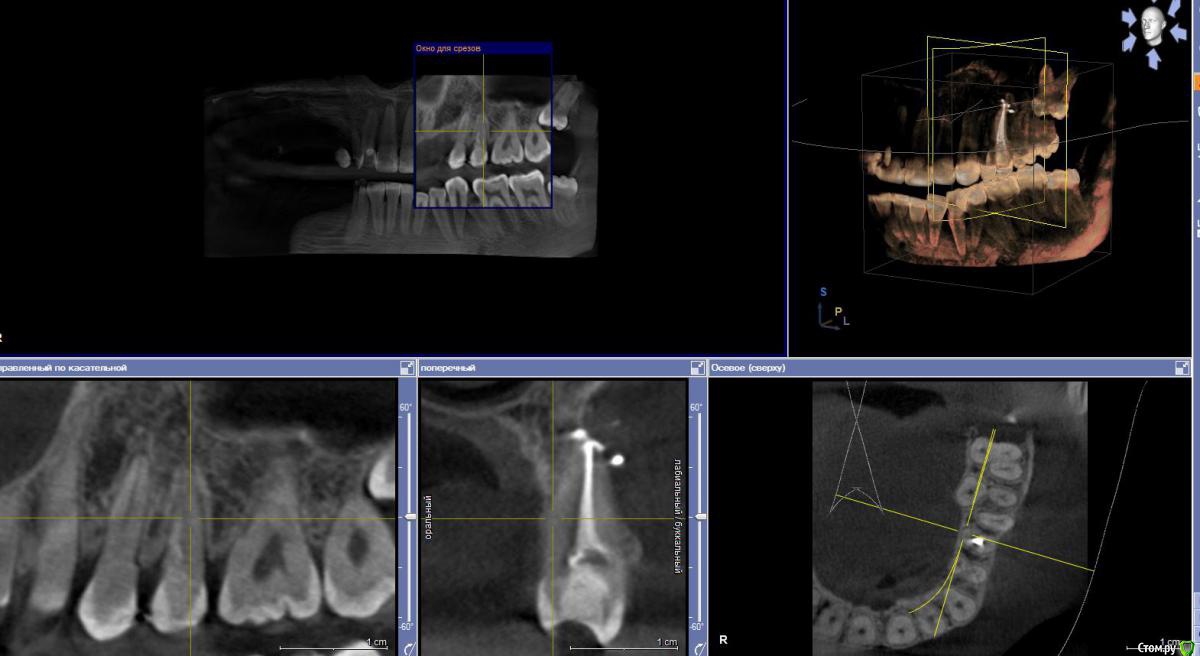

Alexa-a Опубликовано 22 мая, 2018 Автор Поделиться Опубликовано 22 мая, 2018 не знаю удалось ли правильно сделать скриншот КТ зубов, видно что там с пятым зубом почему болит. Есть ли там гранулёма ил что еще? Ссылка на комментарий

Alexa-a Опубликовано 23 мая, 2018 Автор Поделиться Опубликовано 23 мая, 2018 Чтобы ответить на ваш вопрос нужно знать протокол лечения. Причина боли может заключаться в нарушении протоколов лечения или пломбирования или в индивидуальной гиперчувствительности тканей окружающих зубА по КТ не видно? или я не правильно его выложила? А протокол лечения наверное записан в карте, но наверно вы не захотите её читать, так как долго уже лечу этот зуб и много всего с ним делали. Изначально был хронический пульпит, много раз меняли лекарство в зубе, он всё равно болел, потом постоянно запломбировали каналы, потом их распломбировали, перелечивали, в процессе лечения появилась плотная шишка на десне, врач говорит гранулёма, делали депофорез корневого канала три процедуры, после третьей зуб снова вышел в обострение, после того как герметично закрыли зуб. Сейчас врач говорит поставила какое то мощное лекарство с йодом, что оно должно восстановить, но пока боль всё равно остаётся. Ссылка на комментарий